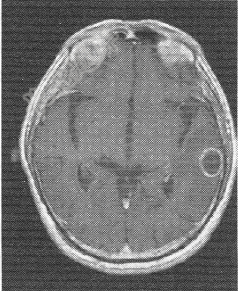

- 单项选择题患者男,72岁。肺癌术后一年余,现出现头晕头痛,MR图像如下,最有可能的诊断是

A、脑转移癌

B、脑膜瘤

C、脑胶质瘤

D、脑炎

E、脑淋巴瘤